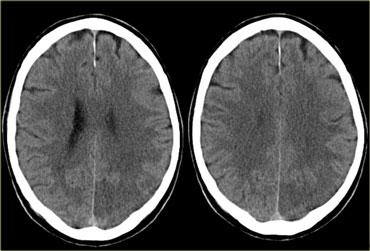

Bên trái là ba lát cắt CT liên tiếp của bệnh nhân tắc động mạch cảnh trong phải.

Tình trạng giảm tưới máu bán cầu phải dẫn đến nhiều ổ nhồi máu vùng ranh giới sâu.

Hình thái nhồi máu vùng ranh giới sâu này khá phổ biến và cần thôi thúc người đọc tiến hành khảo sát các động mạch cảnh.

Bên trái là hình ảnh của bệnh nhân có các ổ nhồi máu nhỏ ở bán cầu phải tại vùng ranh giới sâu (đầu mũi tên màu xanh lam) và tại vùng ranh giới vỏ não giữa lãnh thổ ĐM não giữa (MCA) và ĐM não sau (PCA) (mũi tên màu vàng).

Có bất thường tín hiệu tại động mạch cảnh phải (mũi tên màu đỏ) do hậu quả của tắc mạch.

Ở những bệnh nhân có các bất thường gợi ý nhồi máu vùng ranh giới, cần luôn khảo sát hình ảnh động mạch cảnh để tìm kiếm bất thường tín hiệu.